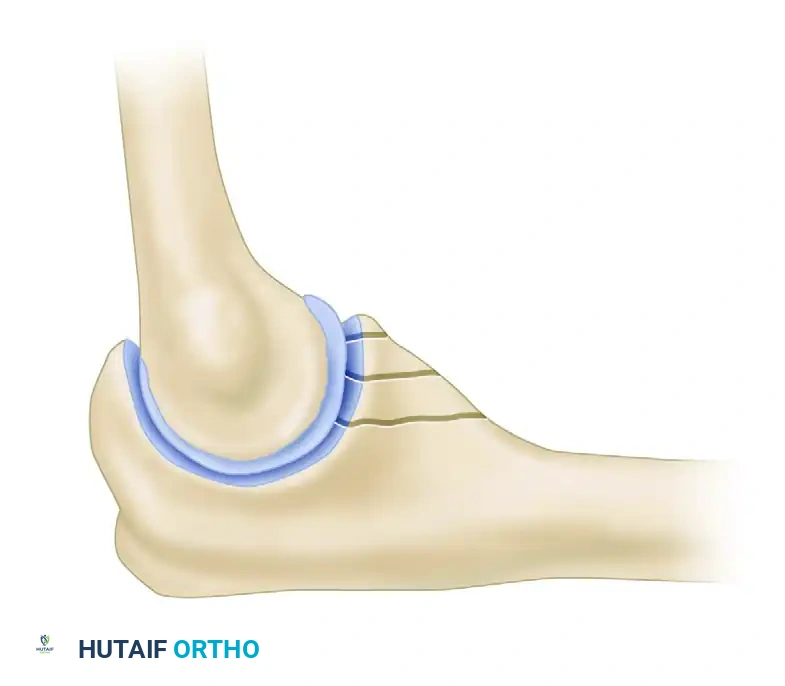

The radial head is a critical secondary stabilizer of the elbow, providing essential resistance against valgus stress and acting as the primary restraint against proximal migration of the radius (longitudinal radioulnar stability). Fractures of the radial head frequently occur following a fall on an outstretched hand, driving the radial head into the capitellum.

- The Safe Zone: The plate must be positioned strictly within the "safe zone" of the radial head to prevent impingement on the proximal radioulnar joint (PRUJ) during forearm rotation. The safe zone is a 110-degree non-articulating arc. It can be identified intraoperatively by marking the midpoint of the lateral radial head with the forearm in neutral rotation, bounded by the radial styloid and Lister's tubercle.